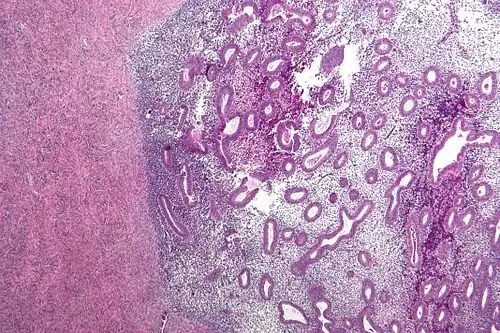

Histopathology

For a histopathological diagnosis, at least two of the following three criteria should be present:[121]

- Endometrial type stroma

- Endometrial epithelium with glands

- Evidence of chronic hemorrhage, mainly hemosiderin deposits

Immunohistochemistry is useful in diagnosing endometriosis as stromal cells have a peculiar surface antigen, CD10, thus allowing the pathologist go straight to a staining area and confirm the presence of stromal cells and sometimes glandular tissue is identified that was missed on routine H&E staining.[122]

Micrograph showing endometriosis (right) and ovarian stroma (left)

Micrograph showing endometriosis (right) and ovarian stroma (left) -